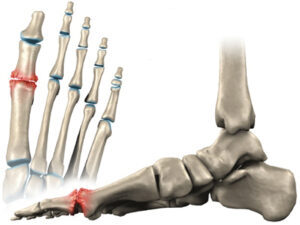

El Hallux Rigidus es una patología que impide la dorsiflexión de la articulación del Hallux (dedo gordo del pie).

Se caracteriza por una artrosis osteofítica, degenerativa y anquilosante de la primera articulación metatarsofalángica. El Hallux Rigidus es uno de los problemas más frecuentes del primer dedo del pie.

- Hipertrofia ósea: Este tipo de sintomatología se manifiesta como una deformidad abultada en la zona del primer metatarsiano. Habitualmente, tiende a confundirse con el famoso “juanete” por su parecido anatómico.

En estadios avanzados, a la hora de caminar no se puede ejecutar el paso correctamente, limitando así la fase en la que el pie despega del suelo (3º rocker o balancín del pie).

Esta articulación es fundamental a la hora de levantar el talón al realizar el paso, así como para saltar o correr. Además, nos ayuda a mantener el equilibrio cuando estamos de pie. Por esta razón, el diagnóstico precoz y un tratamiento adecuado son decisivos para corregir y evitar la evolución del Hallux Rigidus.